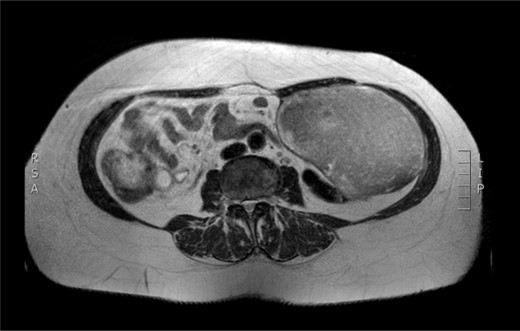

Physical examination revealed a painless, mobile parietal mass on the left anterior abdominal wall, more prominent during cough, of ~13 cm in diameter, with smooth contour and without skin involvement. Laboratory examination including cancer marks showed results within normal limits; hydatid serology (IgG antibodies) was also negative. As ultrasonography results were inconclusive, further imaging with magnetic resonance imaging (MRI) revealed a sizable cystic mass measuring 10 × 13.4 × 11.7 cm, located in the left anterior abdominal quadrant, in the paraumbilical region, between the left internal oblique and the transversus oblique muscle, with projection to the inferior surface of the rectus abdominis. The mass was characterized as a thin-walled cystic lesion, with delayed uptake of intravenous contrast of the wall. High signal intensity was observed on T1-weighted images and low signal intensity on T2-weighted images, with high probability of neoplasia or bleeding (Figs 1–3). No other abdominal or pulmonary lesions were present.

Preoperative MRI—axial plane. T1 weighted image. High sign density of the lesion.